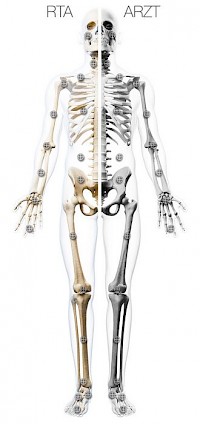

Eine Web-Seite, die für die tägliche Arbeit in der Skelettradiographie, sowohl für Ärzte, als auch für MTA-R sehr nützlich ist.

Am Workflow von MTRAs und Ärzten orientiert, wurde das gesammelte Bildmaterial, geordnet nach Körperregionen, unter Orthorad organisiert.

Während den MTRA's u. a. Informationen zu Lagerung, Röhrenspannung und Kassettenformat zur Verfügung stehen, erhält der Arzt wichtige Informationen zur Röntgenanatomie, Referenzdaten zum menschlichen Skelett und Hinweise bzw. Links zu häufigen traumatologischen und orthopädischen Krankheitsbildern.